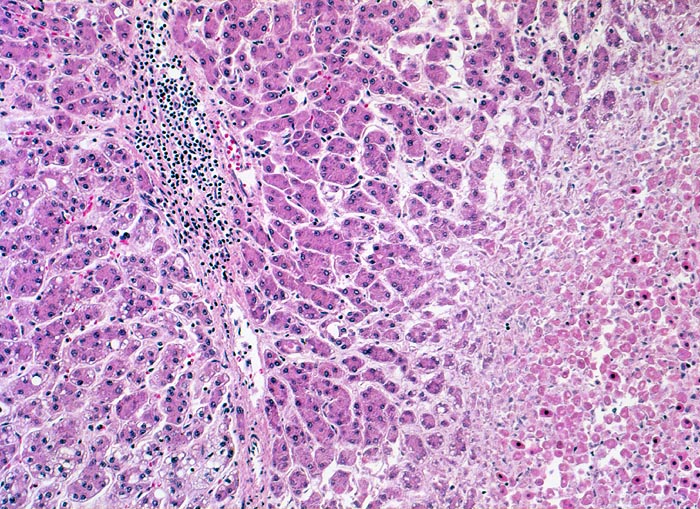

Makroskopisch imponiert das hepatozelluläre Karzinom als solitäre grosse Tumormasse, als zahlreiche zirrhoseartige Knoten oder als scharf begrenzter Knoten mit oder ohne Kapsel. Die tumorfreie Leber ist in der Mehrheit der Fälle zirrhotisch umgebaut. Mikroskopisch bilden die Tumorzellen mehr als 2 Zellen breite Trabekel (> 1237), kompakte Tumormassen (> 1229) oder pseudoglanduläre Strukturen (dilatierte Canaliculi) (> 1212) (> 1199). Desmoplastisches Bindegewebe fehlt meist. Innerhalb des Tumors fehlen Portalfelder. Es finden sich lediglich Arterien. Etwa bei der Hälfte der Karzinome lässt sich intrazytoplasmatische oder intracanaliculäre Galle (> 1238) nachweisen. Immunhistochemisch lassen sich mit einem polyklonalen Antikörper gegen Carcinoembryonales Antigen (CEA) Gallecanaliculi zwischen den Tumorzellen nachweisen. Die Tumorzellen bilden keinen Schleim.

• Die Tumorzellen bilden Trabekel, welche überwiegend mehr als 2 Zellen breit sind und Pseudodrüsen.

• Sinusoidartige Blutgefässe mit Endothelauskleidung verlaufen zwischen den Trabekeln und den Pseudodrüsen.

• Die Tumorzellen erinnern an normale Hepatozyten, sind aber kleiner als die Hepatozyten und die Kern-Zytoplasmarelation ist deutlich erhöht. Das Zytoplasma ist basophiler als das der angrenzenden Hepatozyten.

• Galle ist sichtbar in den Pseudodrüsen.

• Tumorfreies Parenchym mit chronischer viraler Hepatitis (B und D): dichtes chronisches Entzündungsinfiltrat in den Portalfeldern übergreifend auf das Parenchym (Interfacehepatitis). Spärliche intralobuläre Entzündung mit Einzelzellnekrosen (Apoptosen). Fibrose der Portalfelder mit Septenbildung und unvollständigem zirrhotischem Umbau.